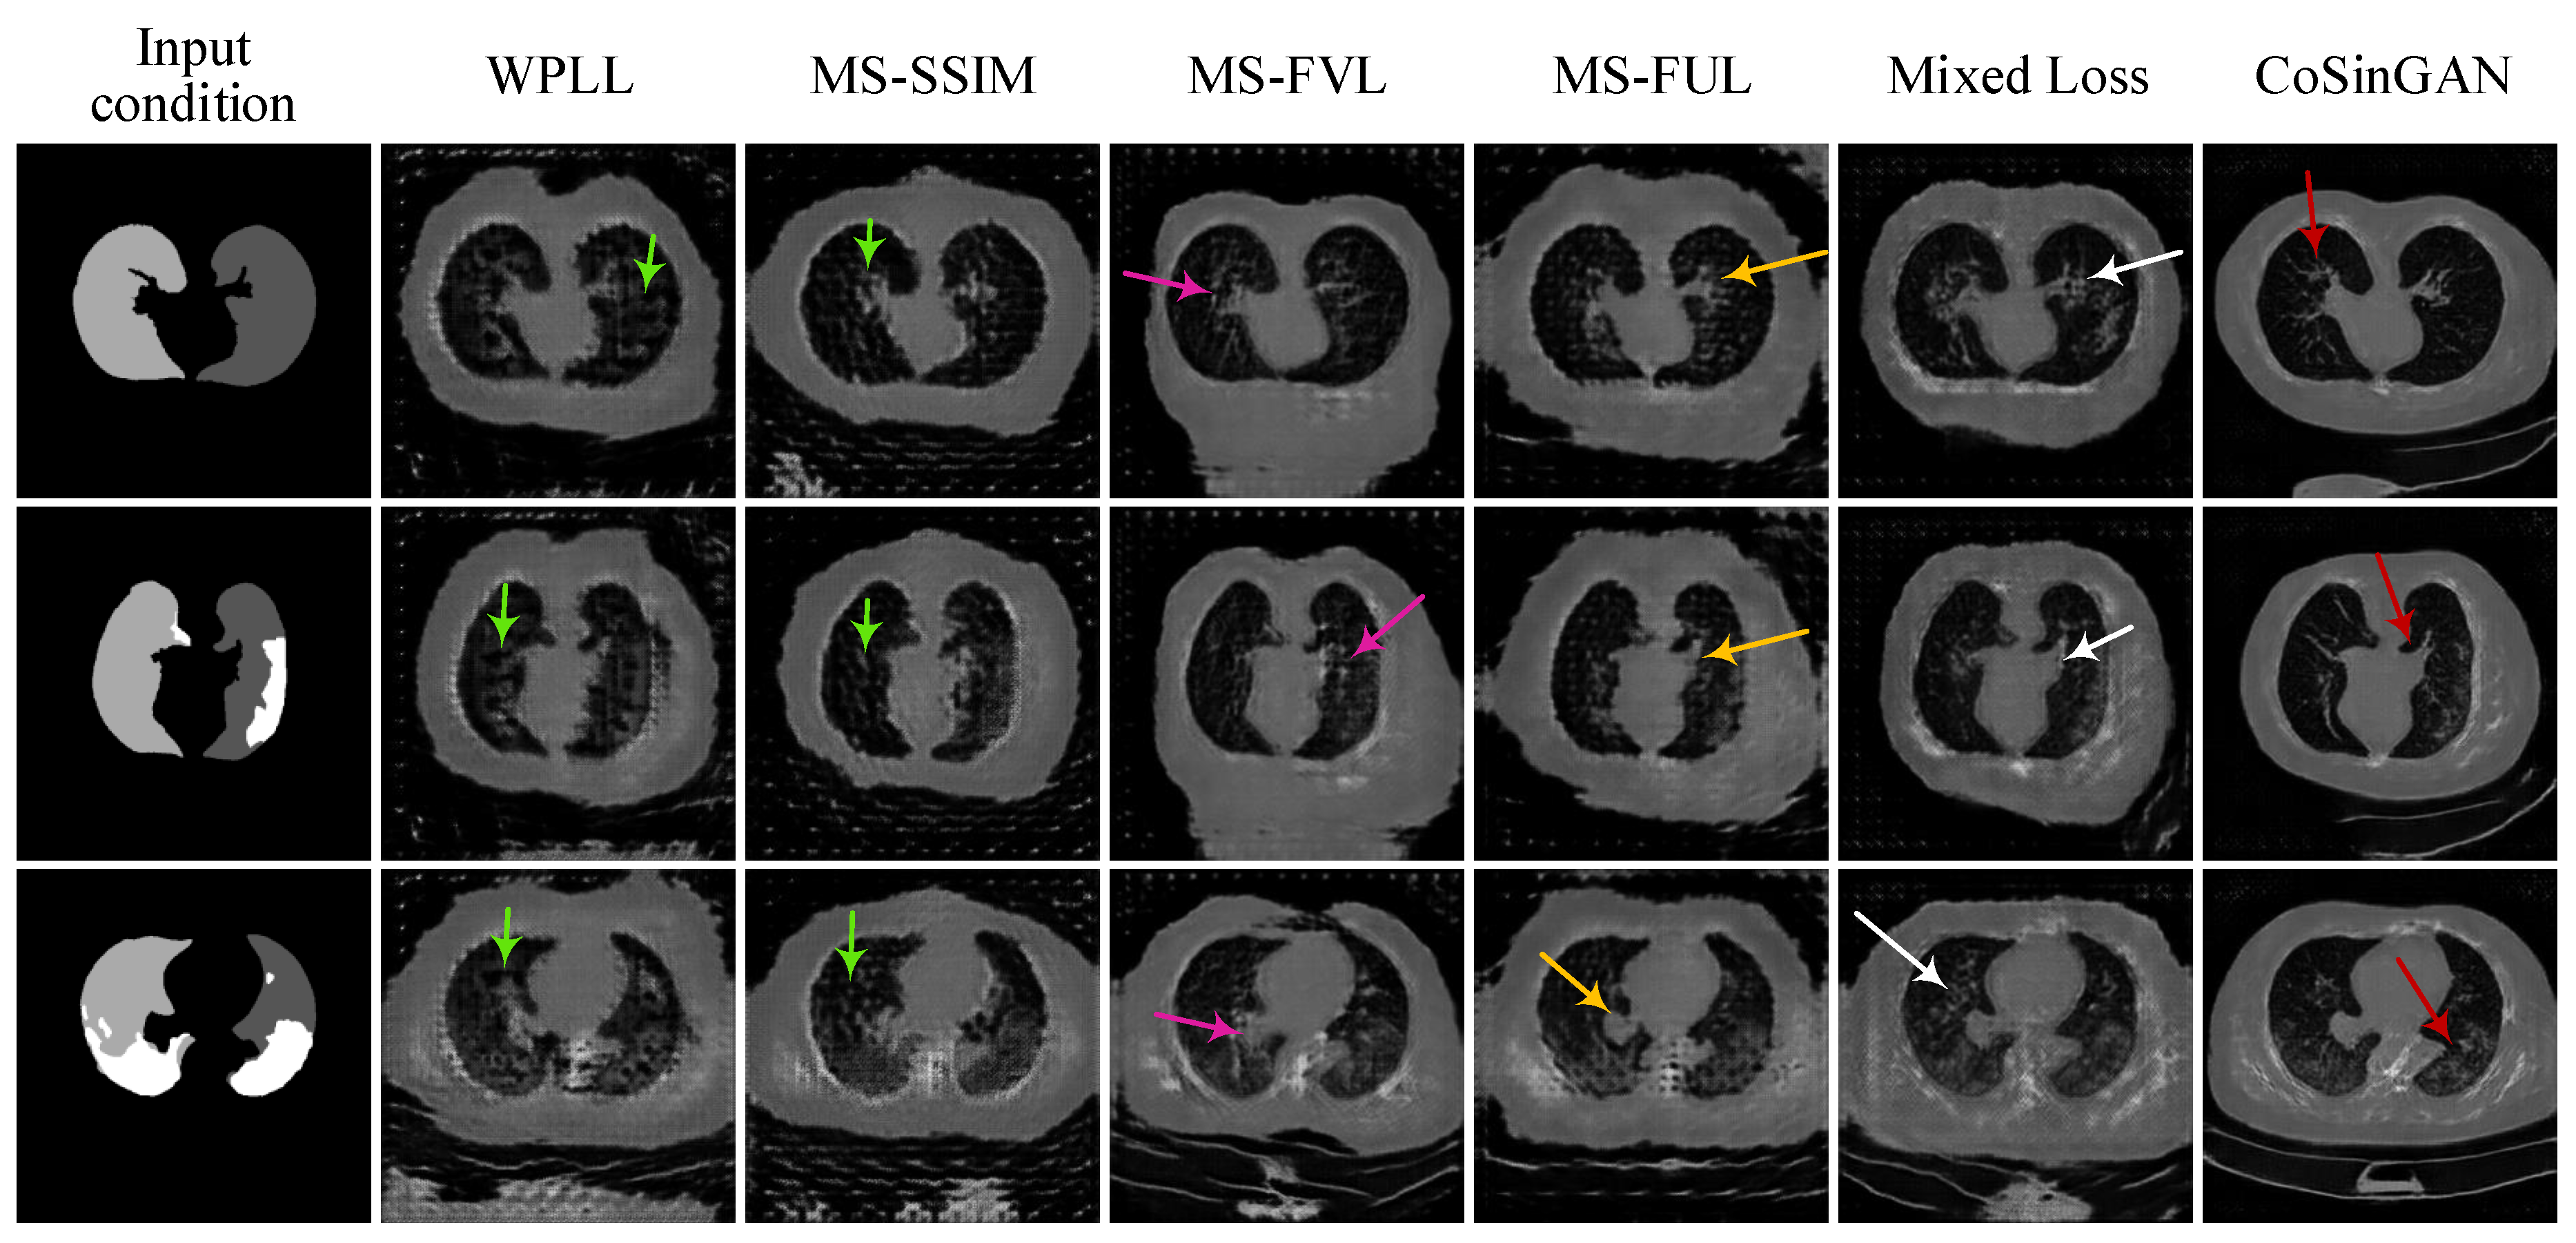

3.1.2. Ablation Experiments

3.1.3. Evaluation and Comparison on Image Quality